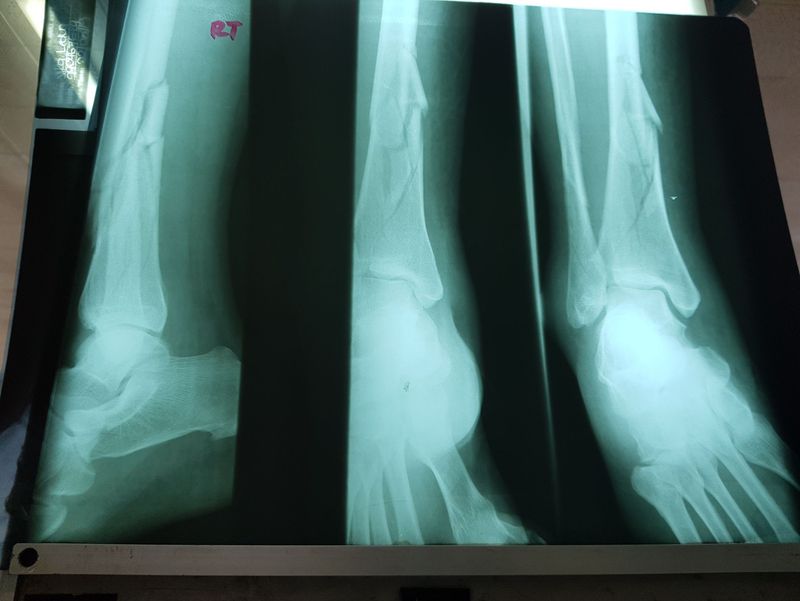

49 year old, history of slip and fall, presented qith this x ray few hours later. What is best management options

#Tibia